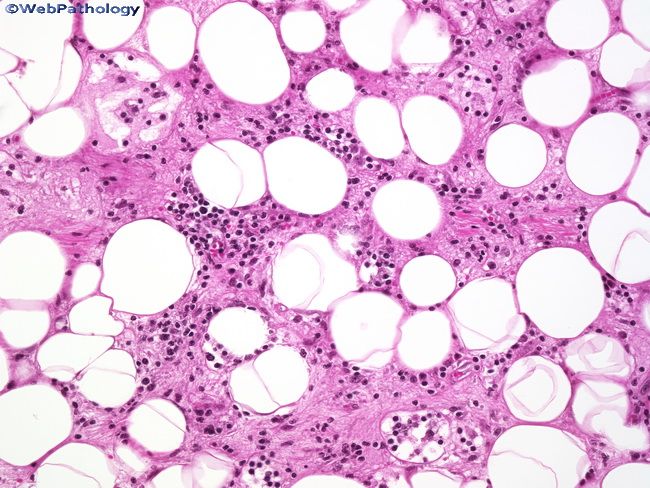

Фото Липомы Молочной

Фото Липомы Молочной 87 фотографий